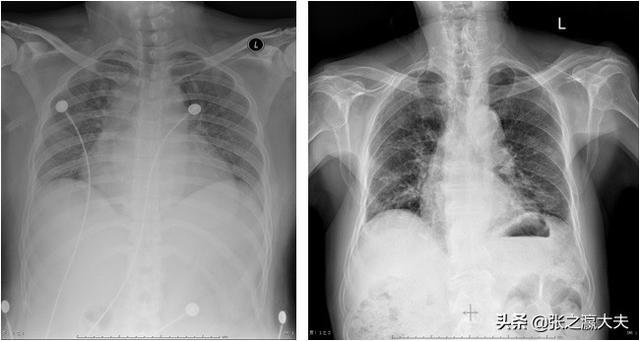

2) Les maladies respiratoires les plus courantes peuvent être dues à la pneumonie, à la bronchite, à la tuberculose, à la dilatation des bronches ; outre les douleurs thoraciques, elles se traduisent également par des expectorations, en particulier dans le cas d'une inhalation profonde ; la toux provoque des douleurs au niveau de la poitrine et de la paroi abdominale.

La douleur thoracique est fréquente car il existe de nombreuses causes de douleur thoracique, telles que la bronchopneumopathie chronique obstructive, le pneumothorax spontané, la pneumonie, la bronchite, etc. dans les maladies respiratoires ; l'œsophagite de reflux, l'ulcère duodénal, la cholécystite, etc. dans les maladies digestives ; la péricardite, la cardiopathie valvulaire, la coarctation aortique, etc. dans les maladies circulatoires ; la dépression, la névrose cardiaque, etc. dans les maladies neurologiques etc. ; herpès zoster, spondylose cervicale, épaule gelée, etc. dans les maladies de la paroi thoracique et du système articulaire. Les personnes souffrant de ces maladies peuvent présenter des symptômes de douleur thoracique qui ne peuvent être définis comme une angine de poitrine.